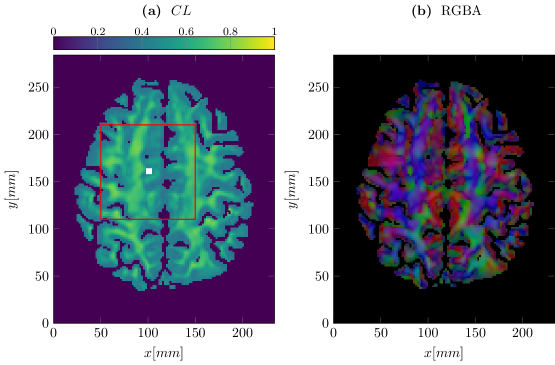

In this numerical experiment we take water diffusion tensors DWsubscript𝐷𝑊D_{W} from a DTI scan of the human brain222Provided by Carsten Wolters (Institute for Biomagnetism and Biosignal Analysis, WWU Münster).. The tensor field is visualized in Figure 4. We use the characteristic length estimate CL(DW)𝐶𝐿subscript𝐷𝑊CL(D_{W}) to obtain the volume fractions via (5.1), which are shown in Figure 4. Additionally the main diffusion direction, i.e the largest eigenvector of DWsubscript𝐷𝑊D_{W}, is shown in Figure 4 as a four-channel color-coded image. The initial tumor mass, marked by the white square in Figure 4, is concentrated in a square of length 5mm5𝑚𝑚5mm

Figure 4: Estimated volume fraction Q=CL𝑄𝐶𝐿Q=CL via characteristic length (subfigure (4)) and an RGBA coded image of the main axis of DWsubscript𝐷𝑊D_{W} (sufigure (4)). The color channels RGB encode the x,y,z𝑥𝑦𝑧x,y,z components of the eigenvector corresponding to the largest eigenvalue of DWsubscript𝐷𝑊D_{W} respectively, while the alpha channel is scaled with CL𝐶𝐿CL. The red square indicates the computational domain, while the white square marks the initial cell distribution.